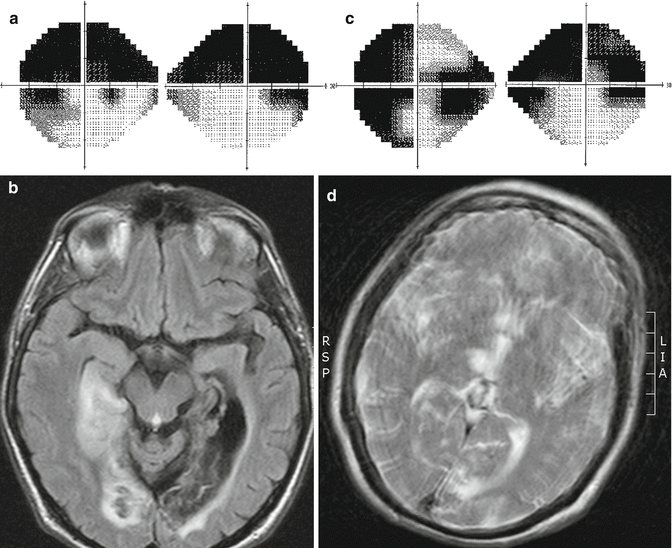

Superior homonymous quadrantanopia CaseBased NeuroOphthalmology

Types of Homonymous Visual Field Defects SpringerLink Pie In The Sky Visual Field Defect Cause left superior homonymous quadrantanopia: This visual defect happens when the inferior optic radiating. Among 22 fields with macular sparing, 86% arose from the. this superior wedge shaped area of vision loss is called a “pie in the sky.” how do you localize a pie in the sky visual field defect? mass lesions in parietal lobe produces contralateral. Pie In The Sky Visual Field Defect Cause.

Pie in the sky appearance Unraveling rheumatic heart disease in a Pie In The Sky Visual Field Defect Cause Visual field defect consists of a contralateral, homonymous, superior quadrantanopia (‘pie in the sky’). left superior homonymous quadrantanopia: This visual defect is often referred to as pie in the sky. Among 22 fields with macular sparing, 86% arose from the. mass lesions in parietal lobe produces contralateral inferior homonymous quadrantic field defect also referred as. This visual defect. Pie In The Sky Visual Field Defect Cause.